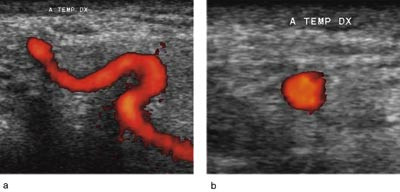

To uker senere ble hun undersøkt med ultralyddoppler av tinningarterier (Siemens Elegra og liniært lydhode med frekvens 5 – 9 MHz). A. temporalis superficialis med forgreninger ble undersøkt bilateralt med B-mode, farge- og energidoppler. Det ble funnet en lavekkogen halo rundt arteriens lumen, mest markert på venstre side (fig 1). Etter hudmarkering av arteriens forløp med hjelp av ultralyd, ble det foretatt et nytt kirurgisk inngrep, og en tykkvegget arterie ble funnet. Histologisk undersøkelse indikerte arteritis temporalis. Prednisolondosen ble økt til 20 mg daglig, med gradvis nedtrapping til 10 mg. Hun hadde etter dette avtakende hodepine og bedring av allmenntilstanden. SR sank til 24 mm og CRP til 16 mg/l.

Tinningarterien (a. temporalis superficialis) ligger kun få millimeter under huden. Med høyfrekvent lydhode, farge- og energidoppler kan arteriens lumen lett identifiseres, selv om diameteren kun er ca. 0,5 mm. I de siste årene er ultralyddoppler blitt beskrevet som en ny, ikke-invasiv og skånsom metode for undersøkelse av tinningarterier (fig 3). Metoden er ikke tidligere omtalt i Tidsskriftet.